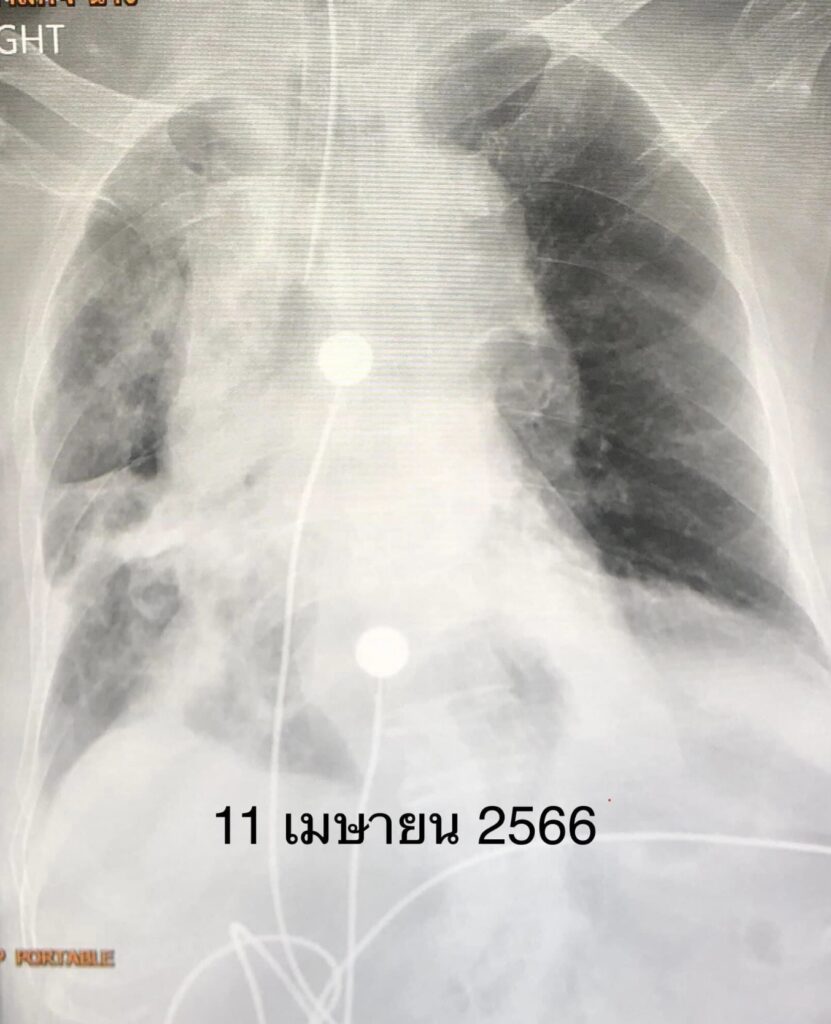

คืนที่เข้านอนในโรงพยาบาล เหนื่อยมากขึ้น เอกซเรย์ปอดพบปอดขวาทั้งข้างขาว (ดูรูป) เชื้อไวรัสโควิด-19 ทำให้เสมหะข้นเหนียวจนอุดหลอดลม ปอดขวาทั้งข้างแฟบ ต้องใส่ท่อหายใจและเครื่องช่วยหายใจ

หลังใส่ท่อหายใจดูดเสมหะ เอกซเรย์ปอดดีขึ้น (ดูรูป) ให้ยาปฏิชีวนะร่วมด้วย 7 วันต่อมาคนไข้ดีขึ้น ถอดเครื่องช่วยหายใจได้